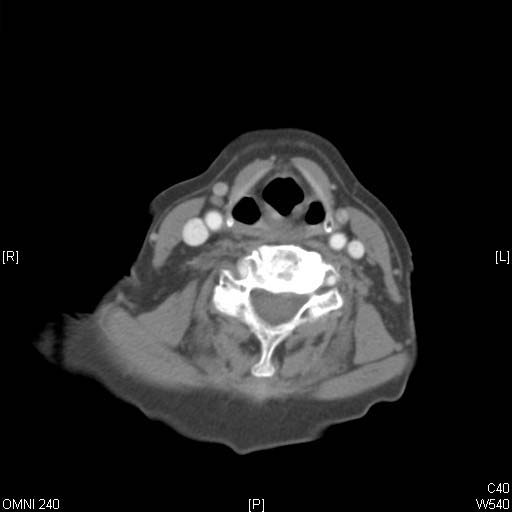

Identify Pyriform sinus